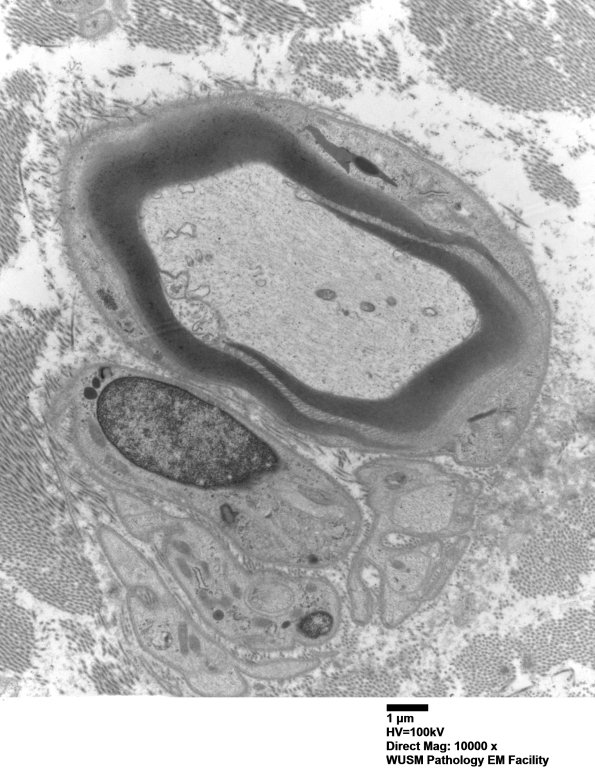

8A1,2 In these images it is clear that the SLC external origin is from the Schwann cell cytoplasm. (Electron micrographs)